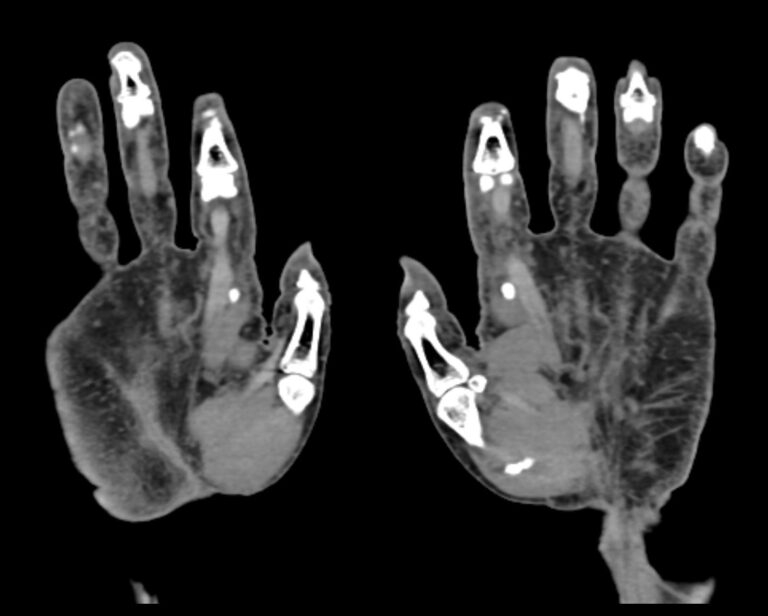

Мультиспиральная компьютерная томография является наиболее точным и информативным методом диагностики травматических повреждений и различных заболеваний костей и суставов пальцев рук. КТ относится к лучевым методам обследования, то есть основан на применении рентгеновского излучения. Быстрота выполнения, неинвазивность (не нужно вмешательство в организм), доступная стоимость делают это исследование незаменимым в травматологии и ортопедии. С помощью КТ проводится диагностика вывихов, ушибов, переломов костей пальцев руки.

При помощи проникающей способности рентгеновских лучей томограф производит послойное сканирование исследуемой области. В результате получаются детальные снимки, а после цифровой обработки данных – подробные трехмерные изображения кисти и пальцев руки.

В наших медицинских центрах КТ пальцев рук выполняется на новейших мультиспиральных компьютерных томографах экспертного уровня TOSHIBA AQUILION. Современное оснащение аппаратов позволяет получать детальные изображения высокого уровня четкости и контрастности, что обеспечивает точность и достоверность диагностики. При этом за счет скоростного мультисрезового сканирования пациент получает уменьшенную дозу рентгеновского облучения.